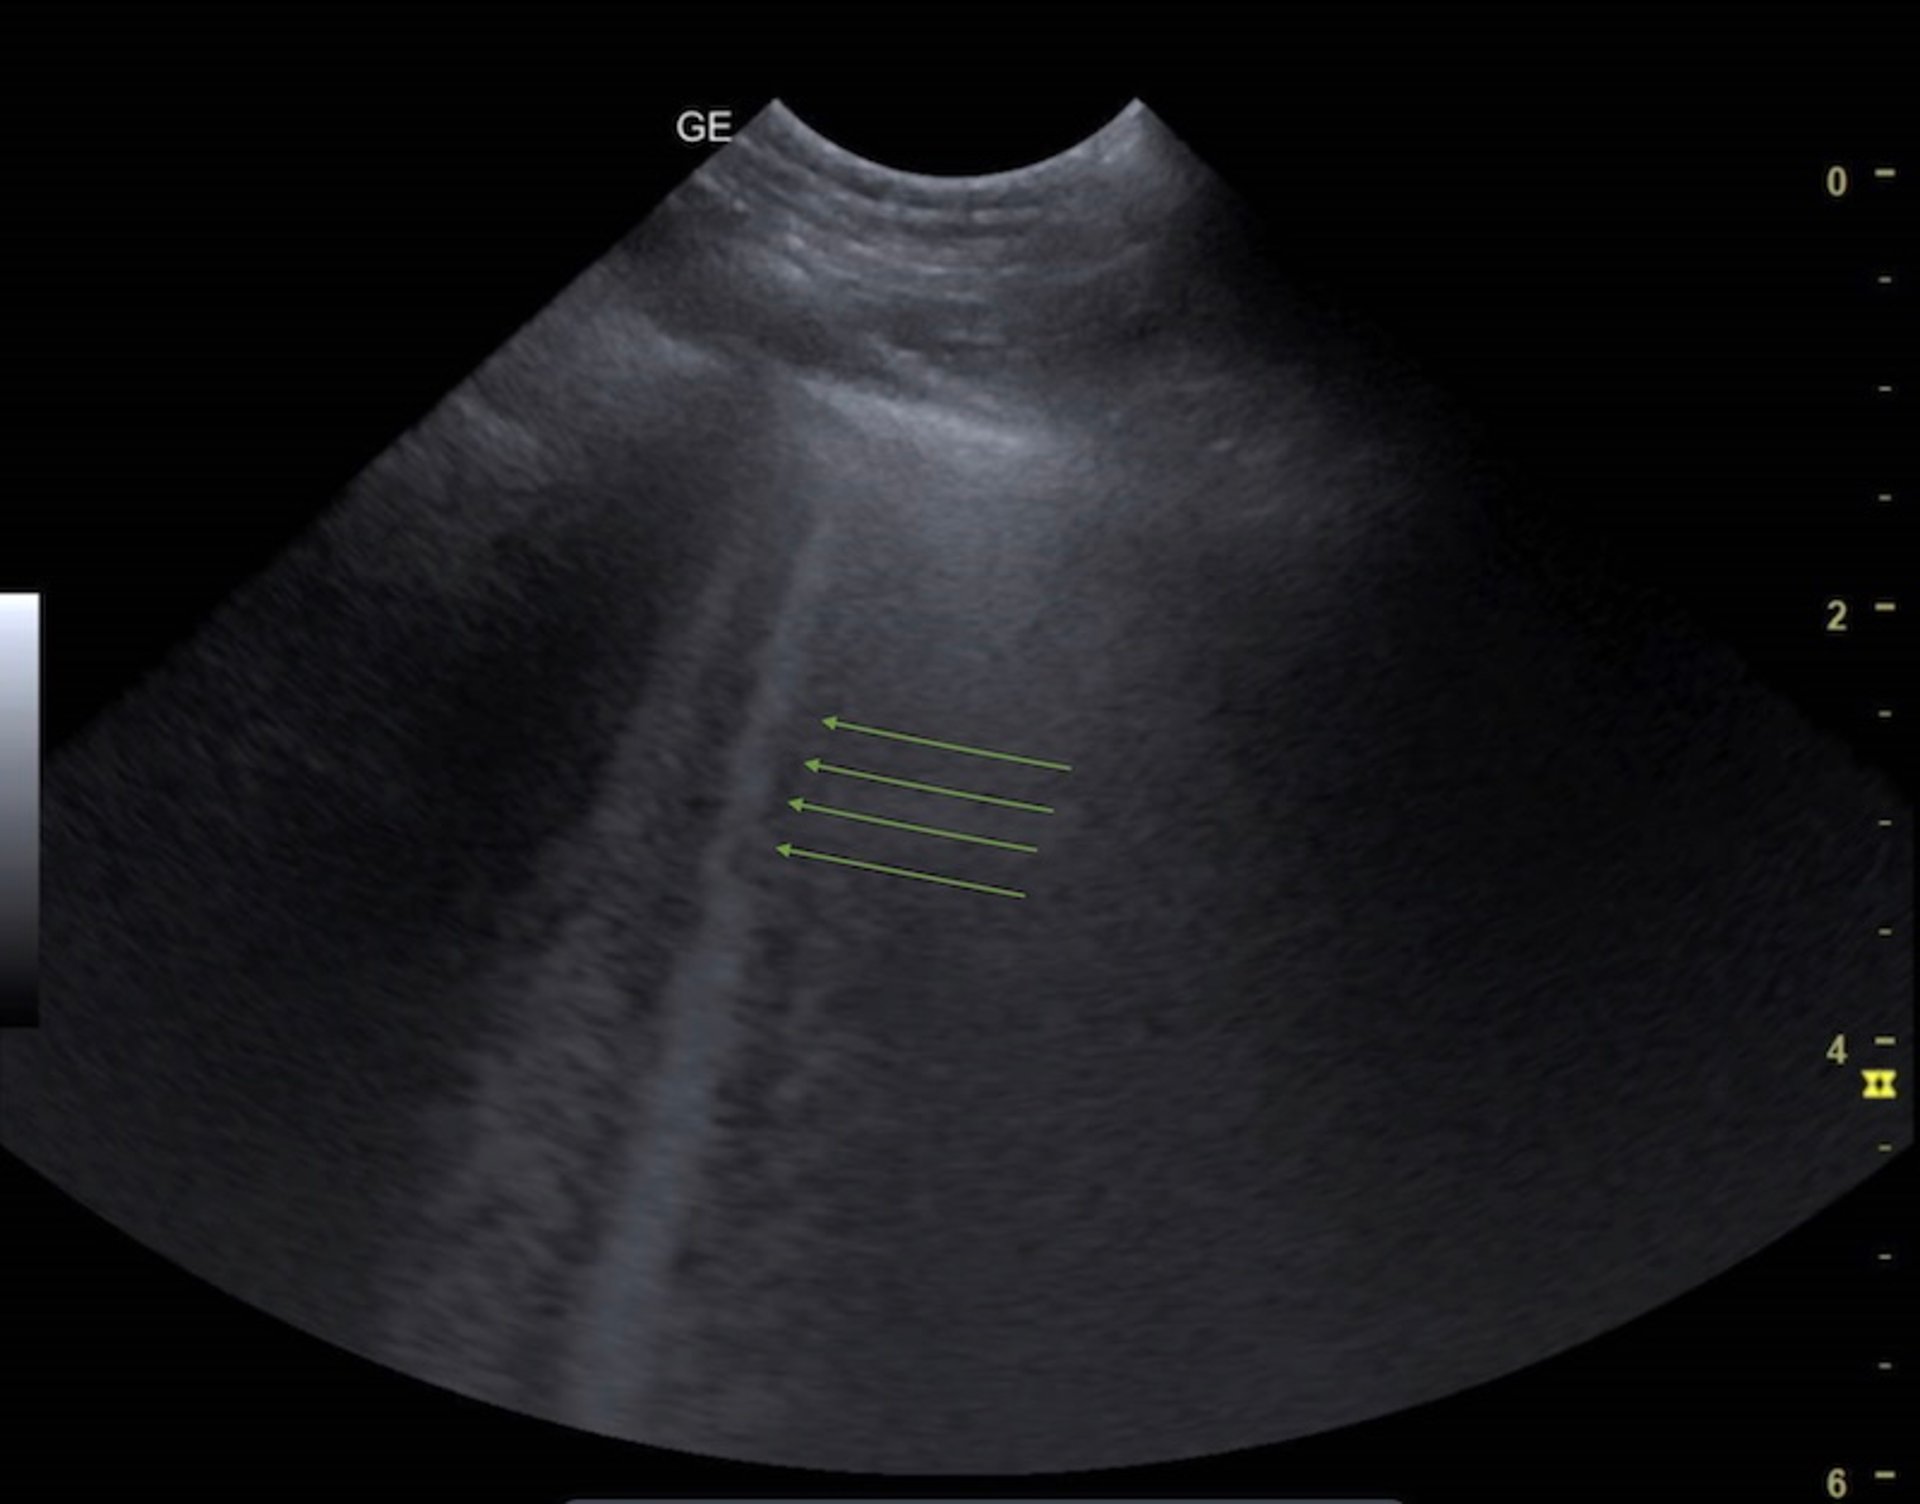

A pneumothorax may be present when the "glide sign" is absent; this is a linear movement noted between the visceral and parietal pleura and requires practice to identify.

B-lines, also called lung rockets, are vertical white projections that arise from the pleural line and occur when there are air-fluid interfaces (see video and image of B-lines). Small numbers of B-lines may be normal; however, large numbers (ie, more than three) of B-lines can indicate abnormal pulmonary fluid (of any origin).

Large amounts of pulmonary fluid often result in irregular lung margins and pleural interface, sometimes called the "shred sign." Large amounts of free pleural fluid are often easy to identify on ultrasonography.